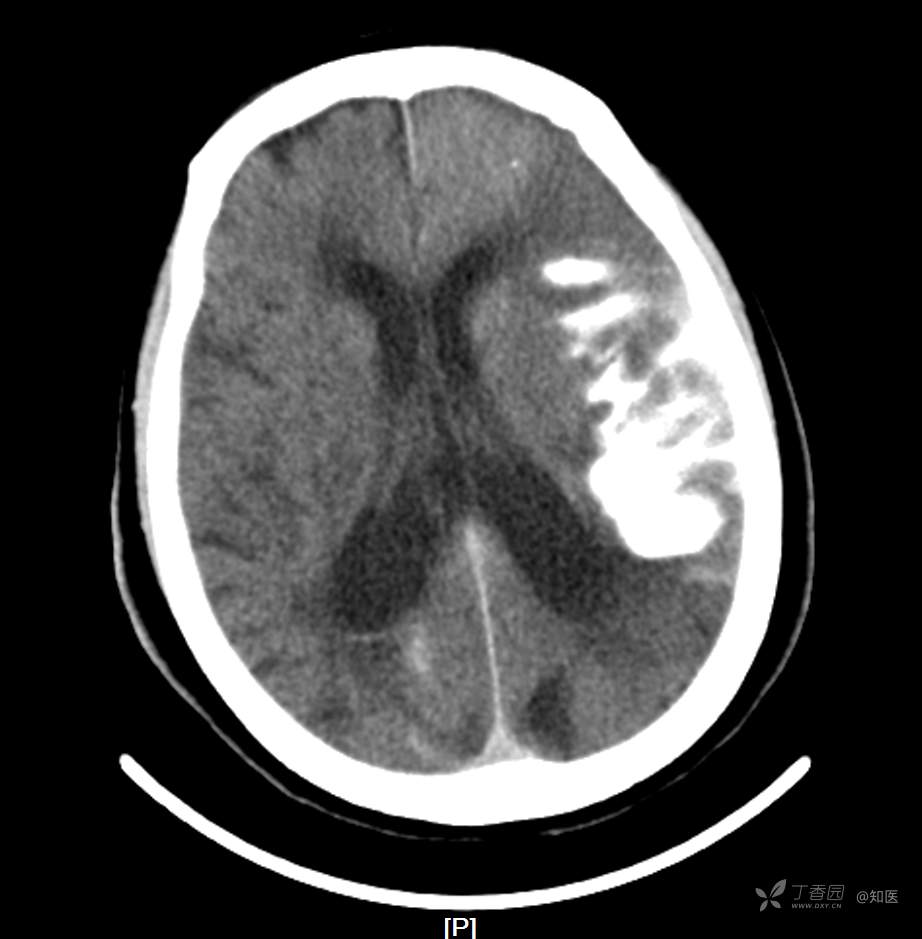

4-22日查房患者呈昏睡状,混合性失语,右侧肢体肌力障碍较入院时加重,胃肠减压引流物为深黄绿色液体,量约150ml。查体:GCS 9分(睁眼反应 3分+语言 1分+运动 5分),NHISS评分23分(意识水平 2分+提问 2分+指令 1分+凝视 2分+面瘫2+左上肢 1分+右上肢4分+左下肢 2分+右下肢4分+语言 3分),昏睡状,查体欠合作,混合性失语,粗测智能查体不配合。双眼闭目紧,双侧球结膜水肿,双侧瞳孔等大等圆,直径约4.0mm,对光反射灵敏,眼球无自主运动,无眼震,右侧鼻唇沟浅,口角向左歪斜。咽部查体不配合。转颈、耸肩查体不配合。伸舌不配合。右上肢肌力1级,右下肢肌力2级,左上肢肌力3级,左下肢肌力4级,四肢肌张力减低。四肢深浅感觉及共济运动查体不配合。右侧巴氏征阳性,左侧巴氏征阴性。颈抵抗。双侧布氏征及克氏征均阴性。辅助检查:头颅+胸部CT:与前片(2021-4-21 13:57)对比,现片示:1、环池、桥前池及大脑镰后部及小脑幕高密度影,考虑出血,较前新发。2、额颞顶叶高低混杂密度影,考虑梗塞伴造影剂残留;左侧大脑中动脉走行区致密影,系术后改变;请结合临床。3、多发腔梗,脑白质脱髓鞘,脑萎缩。4、双肺间质性改变,双肺下叶纤维索条,双侧胸腔微少量积液征象,双侧胸膜增厚。5、主动脉及冠状动脉管壁多发钙化斑块。三线主任医师、二线主治医师查房后示:根据患者病史、体征及辅助检查,目前诊断:1.脑梗死出血转化;2.左侧大脑中动脉次全闭塞;3.左侧大脑中动脉支架植入术后;4.高血压2级(很高危);5.2型糖尿病;6.应激性溃疡伴出血。目前病情及治疗上需注意以下问题:1.患者出血转化,增加脱水剂剂量,调整为20%甘露醇 125ml 每8小时一次、甘油果糖 250ml 每12小时一次,同时结合患者球结膜水肿,白蛋白正常低值,今日给予补充人血白蛋白10g,注意监测电解质等变化。2.患者为蛛网膜下腔出血,给予泵入尼莫地平预防脑血管痉挛。3.患者左侧大脑半球见大片脑白质脱髓鞘,考虑脑白质营养不良,给予维生素B1、维生素B12、维生素C、维生素B6及依达拉奉改善微血管通透性;4.患者出现应激性溃疡伴出血,今日暂禁食,给予泮托拉唑抑酸及肠外营养补充,密切观察消化道出血情况,根据病情变化调整抑酸药物剂量及频次;5.患者卧床,今晨见明显痰多,给予化痰等对症处理,监测血常规及脓毒症2项指标。6.向家属再次告知病情,因患者高龄、既往高血压及糖尿病病史,此次治疗出现出血转化,存在意识障碍加深、病情加重可能。7.密切观察神经系统体征变化。遵嘱执行。

4-23日查房:患者呈中度醒状昏迷,右侧肢体肌力障碍较入院时加重,胃肠减压引流物为黄绿色液体,量约200ml。入院后至今晨入量为4050ml,出量为4850ml。查体:GCS 6分(睁眼反应 2分+语言 1分+运动 3分),NHISS评分35分(意识水平 3分+提问 2分+指令 2分+面瘫3分+左上肢 4分+右上肢4分+左下肢 4分+右下肢4分+感觉 2分+语言 3分+构音障碍 2分+忽视 2分)。中度昏迷。双目睁眼状,双侧球结膜水肿较昨日明显,双侧瞳孔等圆,不等大,右侧直径约3.5mm,左侧瞳孔直径约3.0mm,对光反射灵敏,眼球无自主运动,无眼震。右侧鼻唇沟浅,口角向左歪斜。咽部查体不配合。转颈、耸肩查体不配合。伸舌不配合。四肢肌力检查不配合,右上肢落鞭征阳性,左上肢落鞭征阴性,右下肢不能撑于床面,左下肢可撑于床面,四肢肌张力减低。四肢深浅感觉及共济运动查体不配合。右侧巴氏征阳性,左侧巴氏征阴性。颈抵抗。双侧布氏征及克氏征均阴性。辅助检查:经颅多普勒示:左侧大脑中动脉峰值流速极低,右侧大脑中动脉及双侧大脑前动脉血流速度未见明显异常。头颅CT(2021-04-22):与前片(2021-4-21)对比,现片示:1.环池、桥前池及大脑镰后部及小脑幕高密度影,较前减少。2.额颞顶叶高低混杂密度影,考虑梗塞伴造影剂残留;左侧大脑中动脉走行区致密影,系术后改变;基本同前。请结合临床。3.多发腔梗,脑白质脱髓鞘,脑萎缩。同前。二线主治医师查房后示:患者目前诊断明确。现治疗上需注意以下问题:1.患者夜间体温上升,最高38度,结合患者卧床、痰多、不易咳出,且化验检查提示炎性指标较前明显升高,今日给予头孢哌酮舒巴坦抗感染治疗,同时继续雾化祛痰等。2.因患者应激性溃疡并出血,昨日查胃液潜血阳性,但经给予泮托拉唑抑酸护胃治疗后消化道出血未进行性加重,胃管引流物为黄绿色液体,今日暂继续给予氨基酸、脂肪乳等肠外营养支持,安排再次复查胃液潜血,若转阴可给予肠内营养加强支持治疗。3.患者血压仍有偏高,夜间泵入乌拉地尔控制,今日给予左氨氯地平平稳控制血压,监测血压变化。4.患者昨日血糖波动在6.8-11.4mmol/l,结合其糖化血红蛋白为6.4%,暂不干预血糖,继续监测血糖变化。5.患者意识障碍程度加重,双侧瞳孔不等大,但光反射灵敏,考虑与脑梗死后水肿高峰有关,治疗上继续加强脱水,向家属再次详细告知病情及目前诊疗方案,存在颅内压增高至脑疝形成、呼吸心跳骤停可能,表示理解知情。密切观察生命体征及神经系统体征变化。遵嘱执行。